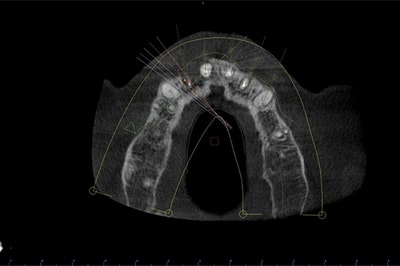

Chirurgie Guidée

L’implantologie moderne évolue vers un positionnement des implants dicté par la prothèse. Il permet et garantit un meilleur résultat esthétique, une meilleure distribution des forces et une hygiène facilitée. La combinaison de l’imagerie 3D et de logiciels de planification autorise des études préliminaires d’une grande finesse. On pourra ainsi visualiser la faisabilité prothétique d’un plan de traitement implantaire.

Au cabinet, pour les cas complexes, après réalisation d’une imagerie 3D (scanner ou cone beam), le cas sera étudié (avec un logiciel de planification), et une solution sera proposée. Dès validation, un guide chirurgical sera confectionné, dans l’absolu respect de la planification. Il permettra de positionner et placer chaque implant dans la position et l’axe pré-défini.

Plusieurs types de guides sont possibles. S’il reste des dents sur l’arcade, nous réaliserons un guide dento-porté (stable et précis). S’il ne reste aucune dent, nous devrons réaliser un guide ostéo-porté.